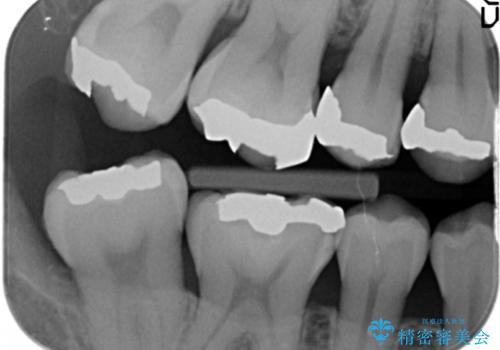

- 笑った時に見える銀歯を白くしたいと希望され来院されました。

現在入っている銀歯を丁寧に除去し、適合の良い精密なセラミックインレーによる修復を行います。